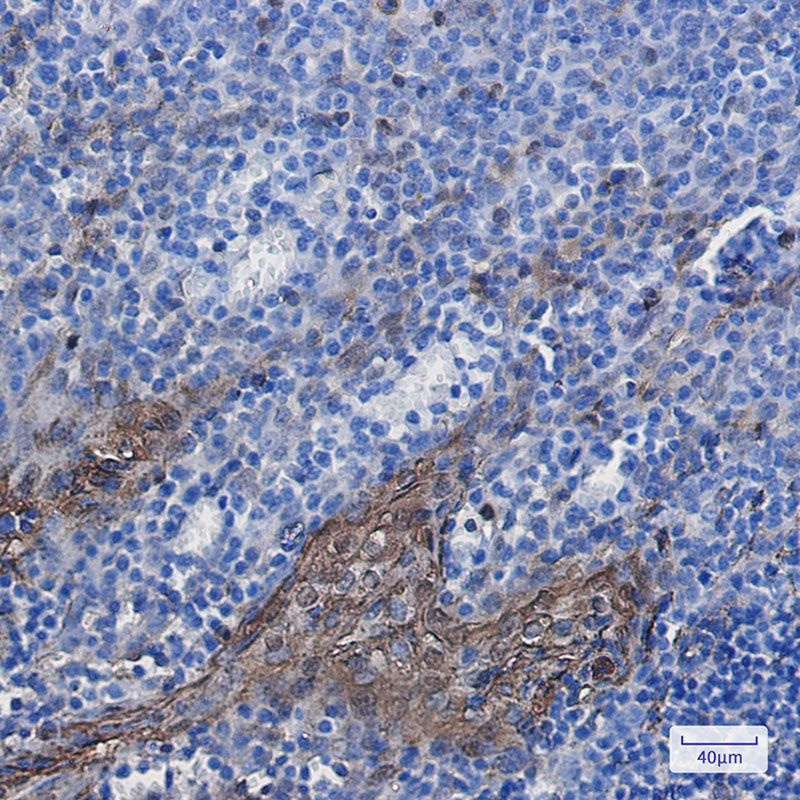

- Immunohistochemistry analysis of paraffin-embedded Human tonsil using Annexin A1 antibody. High-pressure and temperature Sodium Citrate pH 6.0 was used for antigen retrieval.